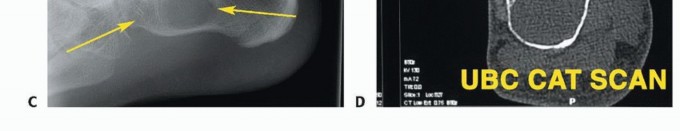

- الأشعة السينية (X-rays): هي الخطوة الأولى لتحديد ما إذا كان الورم عظميًا، وتقييم حجمه، وشكله، ومدى تأثيره على بنية العظم.

- التصوير بالرنين المغناطيسي (MRI): يوفر صورًا مفصلة للغاية للأنسجة الرخوة (العضلات، الأوتار، الأعصاب، الأوعية الدموية) والعظام، مما يساعد على تحديد مدى انتشار الورم بدقة، وعلاقته بالهياكل المحيطة. يعتبر التصوير بالرنين المغناطيسي ضروريًا لتخطيط الجراحة.

- التصوير المقطعي المحوسب (CT Scan): يستخدم لتقييم تفاصيل بنية العظام، خاصة في حالات الأورام العظمية، ويمكن استخدامه لتقييم انتشار الورم إلى الرئتين (في حالات الأورام الخبيثة).

- المسح العظمي (Bone Scan): يستخدم لتحديد ما إذا كان الورم قد انتشر إلى عظام أخرى في الجسم.